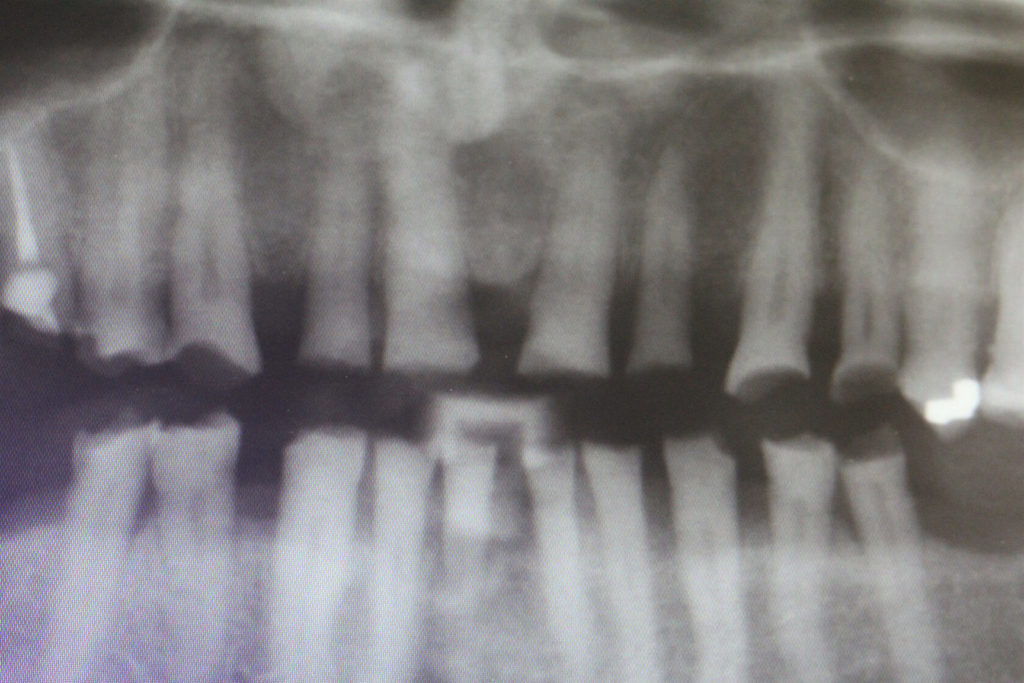

This 50 year old patient was in today for a check-up on his teeth. I had not seen him for 20 months since we restored his lower teeth. We had restored his upper teeth 2 months previous to doing his lower teeth. He came from another neighboring dental office where they don’t do composite rehabs. He has been into this other office for several cleanings since we did his rehab but he smokes, loves his coffee and has lots of stain. Anyway I was wondering how he was making out with his new teeth and he was very satisfied. In his words “no pain or sensitivity or problems”. So I was quite happy with his rehab. His wife came as well and we knew each other from 30 years ago when my daughters and I were riding horses in the same horse club. There were a few air bubbles that I didn’t like and a small open margin that I repaired and that was all he needed to spiffy him up.